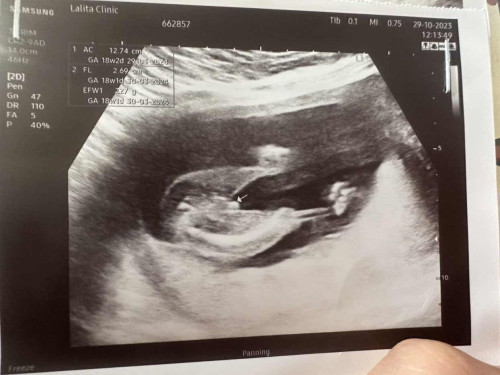

ช่วยดูเพศหน่อยค่าาา

แบบนี้หญิง หรือ ชายคะ 18 สัปดาห์

ผู้ชายค่ะ

ผช.ค่ะ